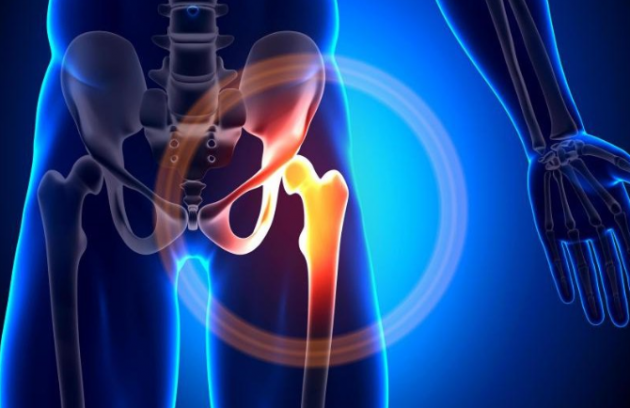

Οστεοαρθρίτιδα Ισχίου

- 1Specialist doctors